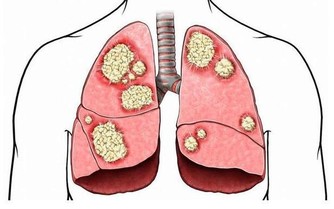

其實很多人到了晚年都是患上了各種疾病,難忍病痛的折磨,也是夠辛苦的;如果是百歲的老人,他們的子女大都已經去世,還要忍受與親人離別的痛苦,是何等的煎熬。